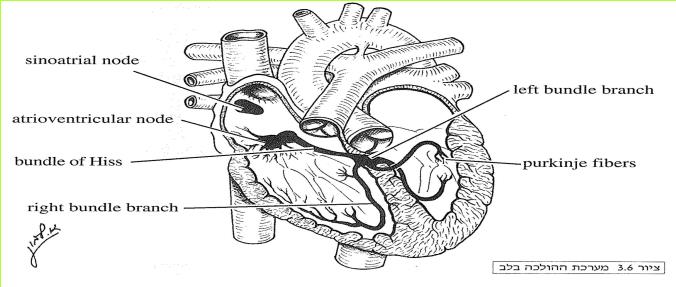

מערכת ההולכה בלב

שריר הלב בדומה לשאר השרירים בגוף, מופעל על-ידי שינוי של מתח חשמלי העובר בשריר. בניגוד לשאר השרירים בגוף המופעלים; על-ידי עצבים השייכים למערכת העצבים (עצבים אלו מובילים את שינוי המתח החשמלי מהמוח לשרירים), הלב מופעל על-ידי מערכת חשמלית פנימית שאינה קשורה למערכת העצבים, הנקראת מערכת ההולכה של הלב (Conduction System).

בחלק העליון של העלייה הימנית מצוי קוצב הלב הנקרא Sinoatrial Node או בשמו המקוצר ה- S.A Node איזור זה מכיל תאים מיוחדים המייצרים שינויי מתח חשמלי בתדירות קבועה. כל שינוי מתח חשמלי מתפשט בעליות מכיוון הקוצב לכיוון המסתמים. התפשטות שינוי המתח החשמלי בעליות גורמת להתכווצות העליות.

המסתמים הנמצאים על גבי מישור אחד בין העליות לבין החדרים אינם מעבירים שינוי מתח חשמלי ולפיכך שינוי המתח החשמלי אינו עובר ישירות לחדרים (ציור 3.6). בעלייה הימנית ליד המסתם התלת צניפי, נמצא איזור הנקרא Atrioventricular Node או בקיצור ה- A.V Node. מאיזור זה יוצא מעין סיב, הנקרא Bundle of Hiss, המעביר שינוי מתח חשמלי בצורה טובה. סיב זה עובר בתוך המישור שבו נמצאים המסתמים, נכנס למחיצה השרירית שבין החדרים ומתפצל לסיבים קטנים יותר המובילים שינוי מתח חשמלי לשני חדרי הלב.

שינוי המתח החשמלי הנוצר ב- S.A Node עובר בעליות וגורם להתכווצותן ומגיע לאיזור ה- A.V Node. באיזור זה שינוי המתח החשמלי מתעכב לחלקיק שנייה ולאחר מכן עובר במהירות לכל השריר בחדרי הלב דרך הסיב היוצא ממנו לחדרים. ברגע ששינוי המתח החשמלי מגיע לחדרים, הם מתכווצים. העובדה ששינוי המתח החשמלי המתקדם בעליות מתעכב ב- A.V Node ורק לאחר מכן עובר דרך מערכת ההולכה לחדרים, מאפשרת לעליות להתכווץ לפני החדרים, דבר החשוב לפעילות התקינה של הלב כמשאבה.

ציור 3.6 מערכת ההולכה בלב

(בספר ציור, היעזר במנחה)

Left bundle branch

Purkinje fibers

Right bundle branch

Bundle of Hiss

Atrioventricular node

Sinoatrial node